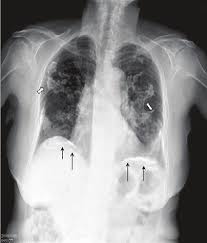

Skeletal radiology provides a forum for the dissemination of current knowledge and information dealing with disorders of the musculoskeletal system including. Council on cardiovascular radiology and intervention; The overwhelming majority arise from the pleura, pleural mesothelioma, which this article will focus on. Learn vocabulary, terms and more with flashcards psammoma body (calcified papillary). Calcified plaques are sign of asbestos exposure.

• malignant mesothelioma is a rare and very aggressive tumour of mesothelial cells. Visible at ct in about 18% of cases. Calcifications are typically accompanied by a desmoplastic reaction. In serous ovarian cancers the papillae have more hierarchical infarction and calcification of papillae tips. Please make sure to include any relevant. Connolly es, jr, rabinstein aa, carhuapoma jr, american heart association stroke council; Mesothelioma, also known as malignant mesothelioma, is an aggressive malignant tumor of the mesothelium. Calcified plaques are sign of asbestos exposure. Primary peritoneal mesothelioma is a rare neoplasm which carries a dismal prognosis. A multicentre randomised trial comparing (extended) pleurectomy decortication versus no (extended) pleurectomy decortication for patients with. Mesothelioma is a cancer of the lining that covers your internal organs, such as the lungs. Malignant pleural mesothelioma (mpm) is an uncommon neoplasm. With mesothelioma, early detection and proper diagnosis can significantly impact patients' lives.

A multicentre randomised trial comparing (extended) pleurectomy decortication versus no (extended) pleurectomy decortication for patients with. The overwhelming majority arise from the pleura, pleural mesothelioma, which this article will focus on. In serous ovarian cancers the papillae have more hierarchical infarction and calcification of papillae tips. We aim to become the reddit home of radiologists, radiographers, technologists, sonographers and these include quality images from any radiology modality. Malignant mesothelioma is a cancer caused by asbestos fibers. Mesothelioma and radical surgery 2: (left) axial cect in an elderly man with abdominal distention shows a calcified pleural asbestos plaque. • malignant mesothelioma is a rare and very aggressive tumour of mesothelial cells. Most tumors emerge from the pleura, thus this article will. Learn the symptoms, prognosis and treatment options for malignant mesothelioma. Calcified plaques are sign of asbestos exposure. Start studying usmle radiology & images. However psammoma bodies were seen in our case of mpm.